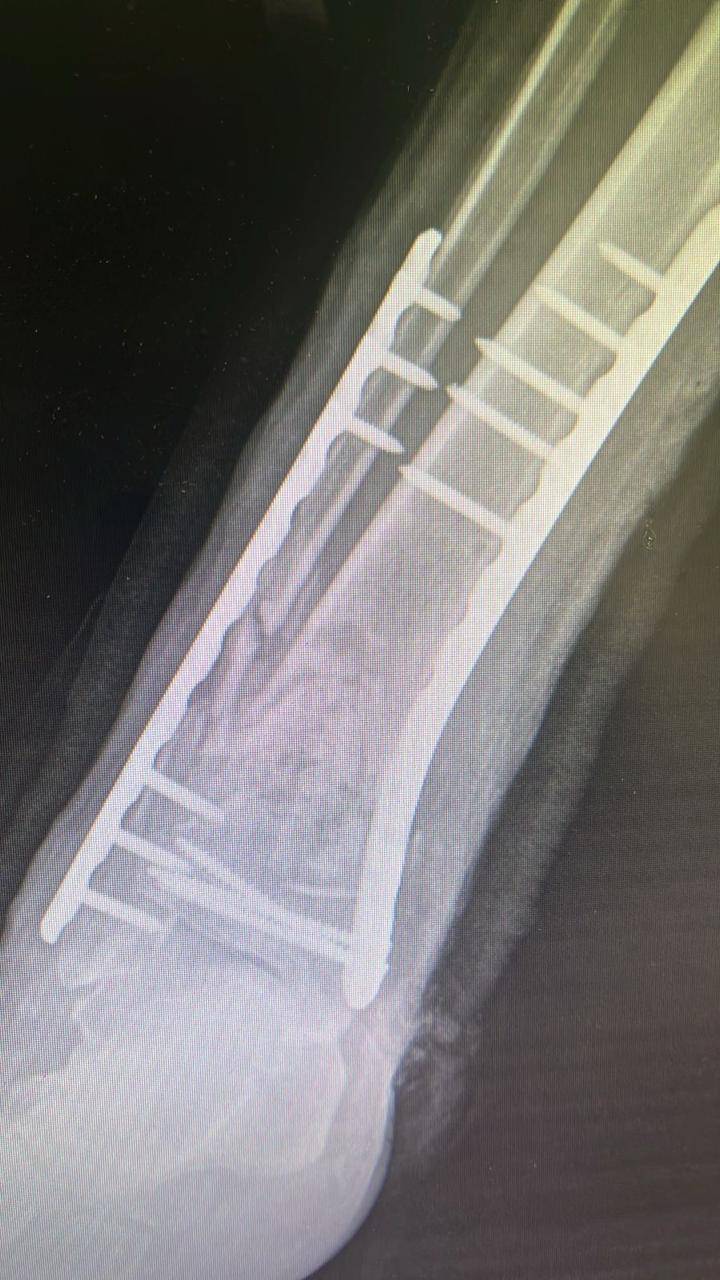

- إجراء عمليات جراحية معقدة و دقيقة في مجال العظام و المفاصل و الكسور و الإصابات ، رغم الضغط الكبير على المستشفى و أعداد المراجعين الكبيرة.

- تطبيق تقنيات جراحية حديثة و متقدمة، و ذلك في ظل التحديات التي يواجهها الفريق بسبب أعداد المرضى و المراجعين الكبيرة.